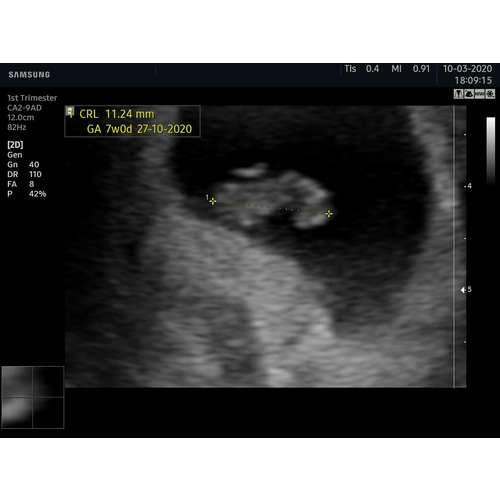

Kimberly die van mij dan? Deze was met 7 weken.uitwendige echo

6 jaar geleden

Als dit de volledige echo foto is die op beeld staat 鉂わ笍

Dan 馃挋馃挋馃挋馃挋馃挋